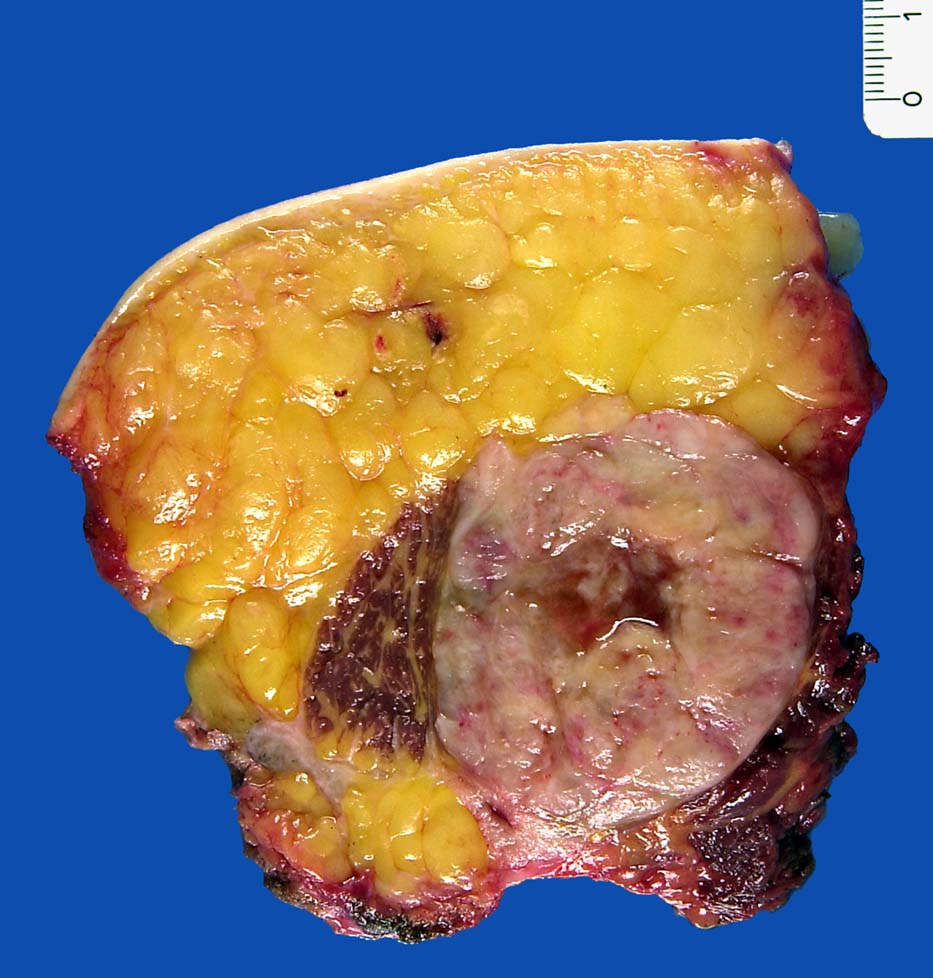

• Am rechten Rand des Präparates komprimierte Skelettmuskulatur.

• Links daran angrenzender scharf begrenzter Tumor mit reichlich myxoidem Stroma.

• Zahlreiche, überwiegend univakuoläre Lipoblasten. Zellkern durch die Lipidvakuole komprimiert und zur Seite verdrängt.

• Zahlreiche krähenfussartig verzweigte Kapillaren.

Makroskopie

Befund

Pathologischer Befund